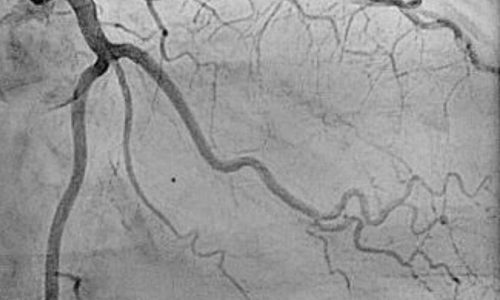

Coronary Angiography

Coronary Angiography is a procedure which is done to look for any blockages in the blood vessels of the heart